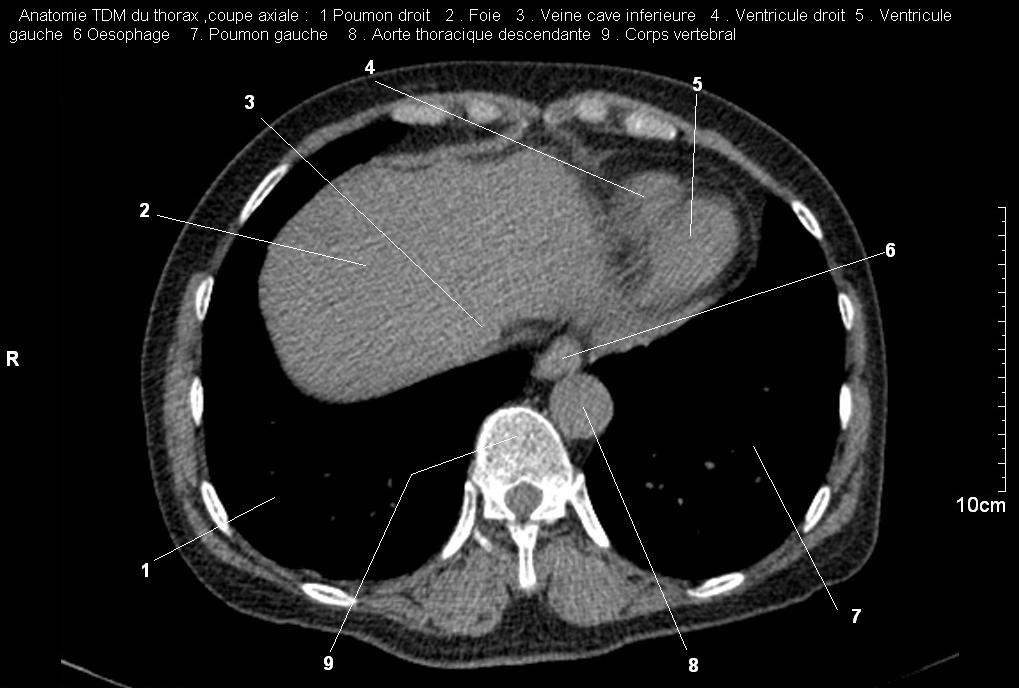

| Images

radiologiques normales du poumon ,la plevre , le diaphragme , et le mediastin

Radioanatomie pulmonaire ( image radiologie

thoracique normale )- La Tomodensitometrie du thorax (

coupes axiales fenetre mediastinale ) |

La fenetres mediastinale permettre

d'etudier anatomie du mediastin et les structures vasculaires

en coupes axiales de 0,5-1cm sur le thorax . Ceux qui

s'installent travers le thorax de C4 a L1, L2

a n'a pas de contrast et se donnent des resutats

suivantes : |